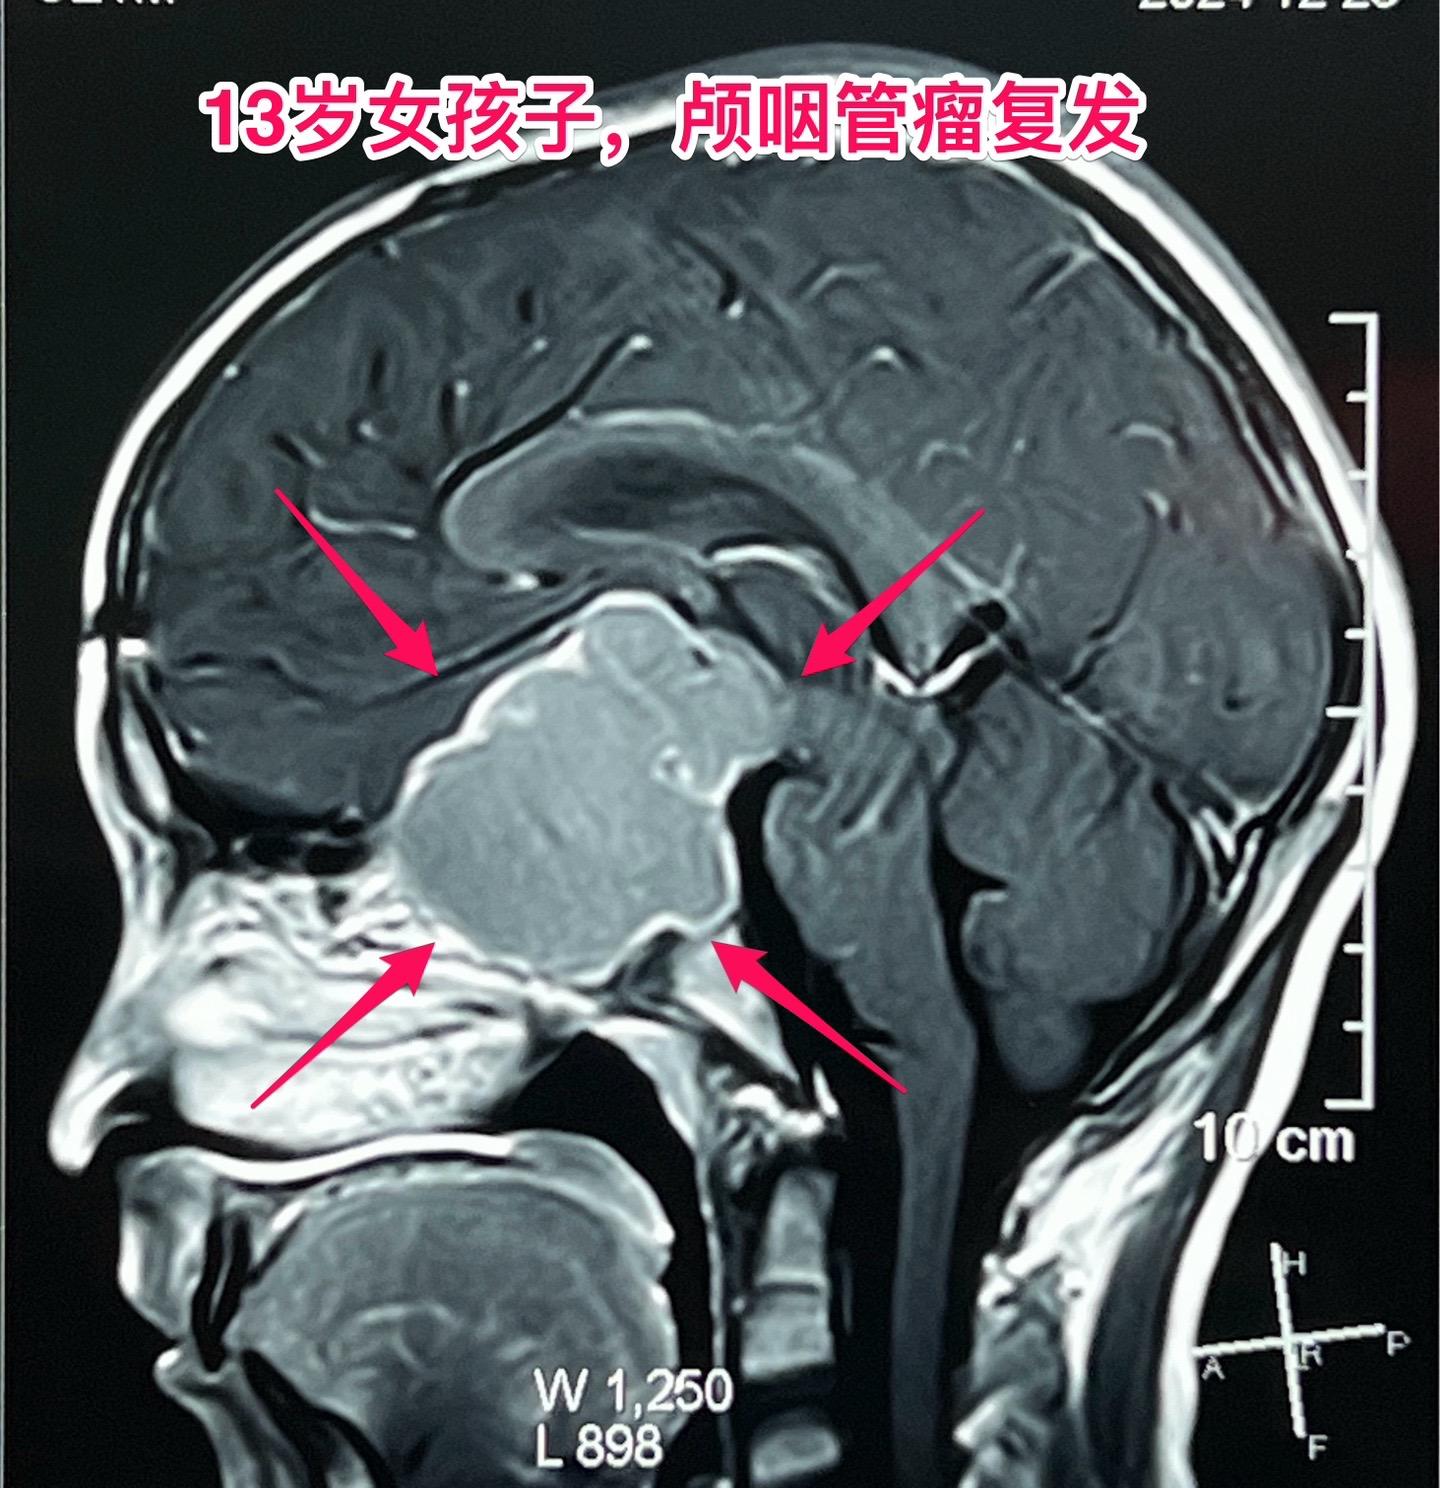

颅咽管瘤两次复发,右眼失明、左眼快失明了。13岁女孩子,因颅咽管瘤之前做过两次开颅手术。肿瘤又复发了,体积很大,垂体窝显著扩大,见图。 12月27日作了手术,将肿瘤完全切除。 这是第三次手术,手术前家长很担心左眼仅有的光感视力会不会变成全盲?会不会出现脑脊液鼻漏? 手术后患者很快就清醒了,左眼视力保住了,也没有脑脊液鼻漏出现。希望肿瘤不再复发。